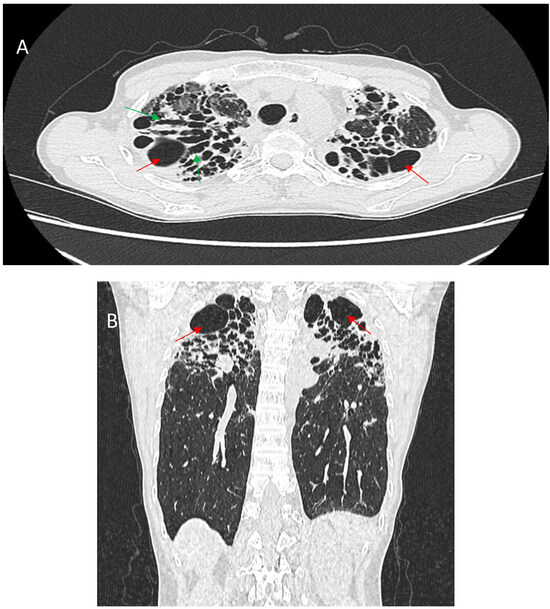

Background: Combined Pulmonary Fibrosis and Emphysema (CPFE) is a distinct syndrome characterized by upper-lobe emphysema and lower-lobe fibrosis, predominantly in older male smokers. Despite often preserved spirometric volumes, patients exhibit severely reduced diffusing capacity and high susceptibility to complications, including pulmonary hypertension (PH), [...] Read more.

Background: Combined Pulmonary Fibrosis and Emphysema (CPFE) is a distinct syndrome characterized by upper-lobe emphysema and lower-lobe fibrosis, predominantly in older male smokers. Despite often preserved spirometric volumes, patients exhibit severely reduced diffusing capacity and high susceptibility to complications, including pulmonary hypertension (PH), acute exacerbations, and lung cancer, contributing to poor prognosis. Purpose: This review aims to synthesize current evidence on CPFE, focusing on clinical phenotype, functional impairment, differential diagnosis, complications, and emerging management strategies, highlighting distinctions from idiopathic pulmonary fibrosis (IPF) and chronic obstructive pulmonary disease (COPD). Methods: A narrative review of observational cohorts, retrospective series, and clinical studies examining CPFE patients was performed. Data on demographics, smoking history, symptomatology, pulmonary function, radiology, comorbidities, complications, and treatment approaches were extracted and integrated. Results: CPFE affects mainly males aged 65–70, with >90% reporting > 40 pack–years smoking history. Dyspnea is the cardinal symptom (>95%), often disproportionate to preserved FVC and TLC, accompanied by chronic cough in 30–70%. Exercise-induced desaturation is frequent, correlating with PH, observed in 47–90% of patients. Pulmonary function tests reveal preserved volumes, normal or near-normal FEV1/FVC, and severely reduced DLCO (35–45%), distinguishing CPFE from COPD and IPF. HRCT confirms the combined emphysematous and fibrotic pattern, critical for differential diagnosis. Acute exacerbations occur in 20–28% of cases, lung cancer in 22–46% (mostly squamous cell), and long-term oxygen therapy is required in >70%. Five-year survival is 35–55%, lower than emphysema alone and comparable or worse than IPF. Management focuses on smoking cessation, antifibrotics, oxygen therapy, and complication-specific treatments, and selected patients may undergo lung transplantation. Conclusions: CPFE is a clinically and functionally unique entity with a high burden of pulmonary and systemic complications. Accurate recognition using HRCT and DLCO, along with early intervention and tailored management, is essential to improve patient outcomes and guide prognostic stratification. Full article